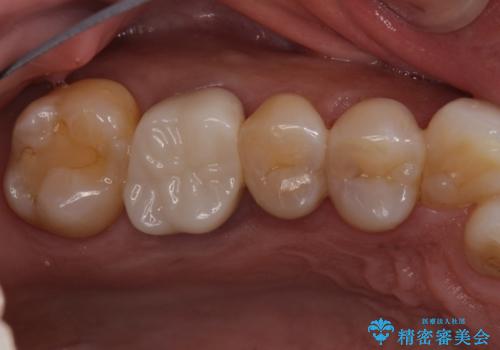

腫れもなくなり、見た目もきれいになったため、右上もご希望されて計3本の歯を治療しました。患者様には大変満足して頂きました。